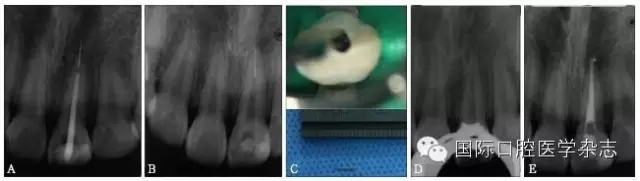

超聲技術(shù)作為經(jīng)典且有效地取出分離器械的方法之一,具有獨(dú)到的優(yōu)勢。超聲工作尖可以在顯微鏡直視下在根管內(nèi)運(yùn)動(dòng),且能夠不對(duì)稱地去除分離器械周圍的牙本質(zhì),若只在分離器械一側(cè)局部運(yùn)動(dòng)即能取出分離器械,則有利于保存根管壁較薄一側(cè)的牙本質(zhì),減少牙本質(zhì)的損失。此外,當(dāng)器械分離于根管中下段甚至超出根尖孔,而分離器械較松時(shí),可用超聲工作尖伸入根管內(nèi)分離器械旁邊,利用水流與超聲振動(dòng)將分離器械帶出根管(圖11)。

A:X線片示上頜中切牙根尖部有一分離器械,器械超出根尖孔;B、C:超聲結(jié)合水流沖洗,有時(shí)可意外取出分離器械;D:X線片示分離器械被取出;E:根管預(yù)備并充填至根尖。

圖 11 當(dāng)器械分離于根管中下段甚至超出根尖孔,而分離器械較松時(shí),超聲器械有獨(dú)特的優(yōu)勢